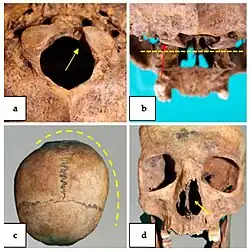

No primeiro caso, analisado por Herrerín e colaboradores (2022)[2], é apresentado o crânio de um homem de 22 anos da coleção de esqueletos de Olóriz (Espanha), ao qual foi feita uma análise macroscópica e radiológica (através da tomografia computadorizada) e que mostra características típicas da síndrome de Klippel-Feil, como a fusão de duas ou mais vértebras.

Na vista frontal, observou-se uma assimetria lateral importante, com desvio dos ossos nasais e septo nasal para a direita, a mesma assimetria afetou também as órbitas (figura 1b). Na norma posterior, a assimetria também era evidente, com importante deslocamento lateral da sutura sagital e do ponto craniométrico lambda, enquanto a sutura lambdoide parecia visível e não obliterada (figura 1c).

Na vista inferior o crânio apresentava assimetria de todo o maciço facial com deslocamento muito significativo do plano sagital mediano (figura 2).

Na norma posteroinferior nota-se uma fusão atlanto-occipital (figura 2), com fusão do maciço lateral e um arco posterior de aparência normal do atlas. O processo odontóide também se encontra fundido com o arco anterior e a massa lateral direita do atlas, para além disso, é ainda observável uma sinostose do canal vertebral.

Um esqueleto de um individuo com cerca de 25 anos que foi um soldado do exército real jugoslavo, apresenta fusão do atlas e do áxis o que causava limitação na rotação do pescoço, identificada como síndrome de Klippel-Feil tipo II (Leggio e colaboradores, 2022)[10]. Na análise craniana verificou-se uma assimetria do parietal e occipital causando deformação no crânio, observou-se também uma hipoplasia condilar occipital bilateral e assimétrica do foramen magnum (figura 4), onde se verifica que, embora os côndilos estejam completos estes são assimétricos e deve-se à fusão das vértebras anteriormente referidas. Há também um desvio no septo nasal (figura 4), mas pode ter ocorrido devido a outros fatores que não a síndrome. Analisando a coluna vertebral, verificou-se que este individuo tinha escoliose e spina bifida occulta, sendo estes sintomas da síndrome de Klippel-Feil (tal com citado em Leggio et al, 2022)[10].